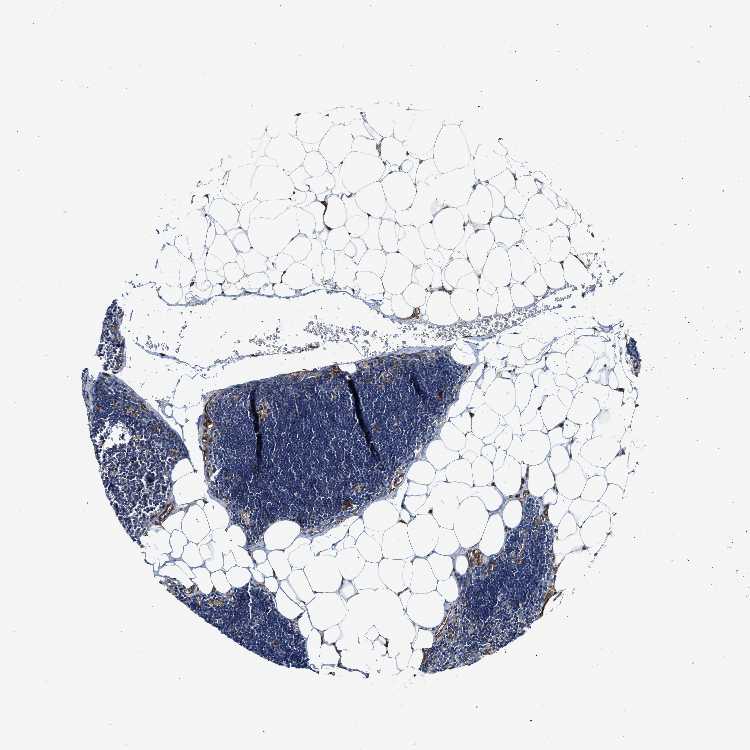

LYMPH NODE - Antibody stainingi

Antibody staining in the annotated cell types in the current human tissue is reported as not detected, low, medium, or high, based on conventional immunohistochemistry profiling in selected tissues. This score is based on the combination of the staining intensity and fraction of stained cells.

Each image is clickable and will lead to virtual microscopy that enables deeper exploration of all samples and also displays staining intensity scores, fraction scores and subcellular localization as well as patient and tissue information for each sample.

Antibody HPA013606Antibody HPA017964Antibody CAB015334Antibody CAB016402

Germinal center cells LowMediumLowMedium

Non-germinal center cells MediumHighMediumHigh